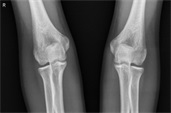

(图:刘先生治疗前的情形)

来到医院后,杜爱华主任为刘先生进行系统规范的检查,检查报告显示刘先生C-反应蛋白26.15mg/L,血沉49mm/L,血小板450×109/L,抗CCP抗体150RU/ml(正常参考值〈12RU/ml)。而且刘先生的膝关节开始肿胀,关节间隙狭窄,关节面边缘模糊不清,遭受到严重的破坏,凹凸不平或囊状透亮区,肘关节、膝关节肿胀,膝关节伸不直,脚踝关节活动受限。